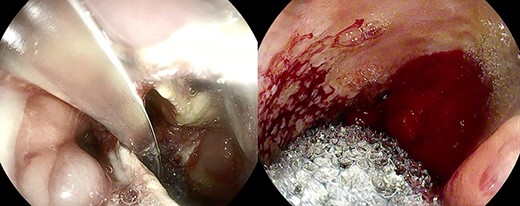

Large anastomotic leakage after minimally invasive esophagectomy opening to a cavity in the pleural space of 8 cm in size.

On the third postoperative day (POD), inflammatory indexes increased (CRP 178.2 ng/mL). On the fourth POD, the endoscopy and CT scan showed a large anastomotic leak involving 75% of the anastomosis and opening to a giant wound cavity in the pleural space of 8 cm in size; fibrosis and abundant necrotic tissue were also present (Fig. 1).